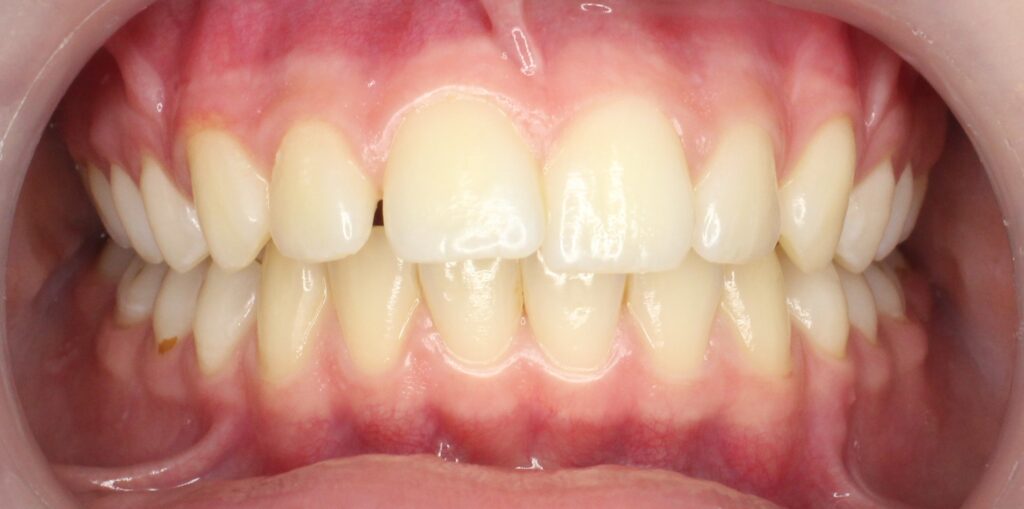

Результаты

результат лечения брекет-системой